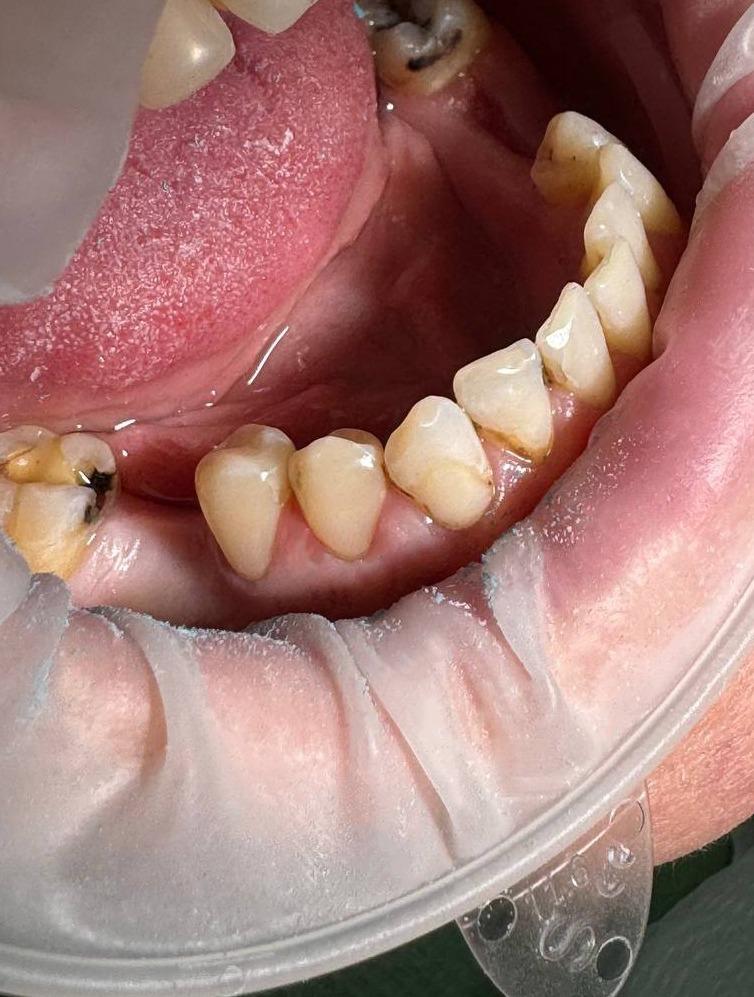

Пациент обратился с жалобами на эстетический дефект. Полная санация полости рта у пациента. Проведено лечение кариеса всей полости рта.